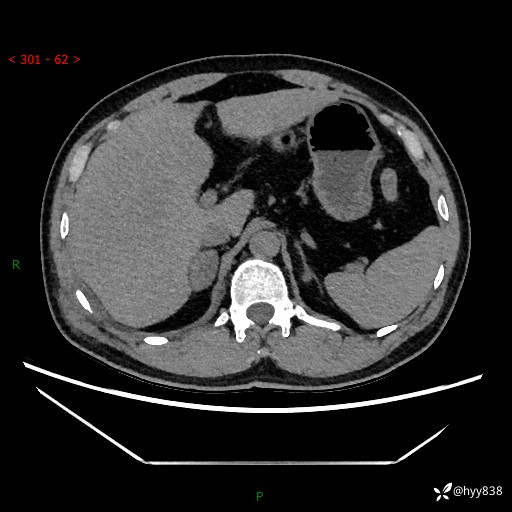

现病史:患者9月4日摔伤在深圳市宝安区中心医院行CT检查提示右侧肾上腺区结节(38*27mm),复查B超提示右侧肾上腺区可见一61*24mm异常低回声团,建议进一步检查。进一步完善增强CT后提示:右侧肾上腺区肿块及周围渗出改变,大致同前,考虑肾上腺腺瘤,不除外瘤内出血可能,否认阵发性头晕、头痛、出汗、乏力等不适,门诊以“ 右侧肾上腺肿瘤”收入住院。 起病来,患者精神、食欲、睡眠可,大便通畅,小便如上述,体力体重无明显改变。

肾上腺CT平扫